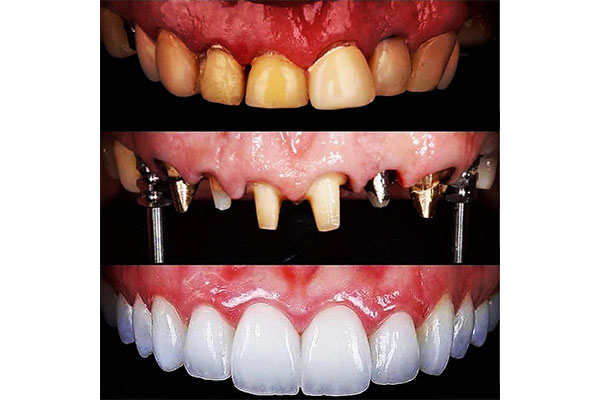

قیمت ایمپلنت دیجیتال در تهران سال 1401

همانطور که اشاره کردیم، ایمپلنت دیجیتال یک راه و روش نوین و بسیاری پیشرفته در حوزه دندانپزشکی مدرت است. در این روش به کسانی که دندان خود را از دست دادند این امکان را می دهد که بدون ریشه، بیمار دندان کاشت شده داشته باشد. گستردگی و سرعت بالای ایمپلنت دیجیتال باعث شده است تا قیمت بیشتری نسبت به سایر روش ها داشته باشد. با استفاده از این مدل از کاشت دندان، ظریف ترین و بدون درد ترین راه برای ایمپلنت را تجریه خواهید کرد. مزیت های ویژه این روش باعث می شود تا ارزش هزینه بیشتر نسبت به سایر مدل های کاشت دندان را داشته باشد.

ایمپلنت دیجیتال یکی از بهترین روش های کاشت دندان است. در این روش دقت و ظرافت بسیار بالایی وجود داشته و باعث می شود تا دندان ها به طبیعی ترین شکل ممکن کاشته شود. همچنین بیماران از کاشت ایمپلنت دندان به صورت دیجیتال رضایت بیشتری نسبت به روش های دیگر، دارند. در این مقاله سعی کردیم مراکز ایمپلنت دیجیتال در تهران را به صورت کامل برای شما گردآوری کنیم. اگر شما نیز تجربه ای از انجام این روش از کاشت دندان دارید، نظرات خود را ارسال فرمایید